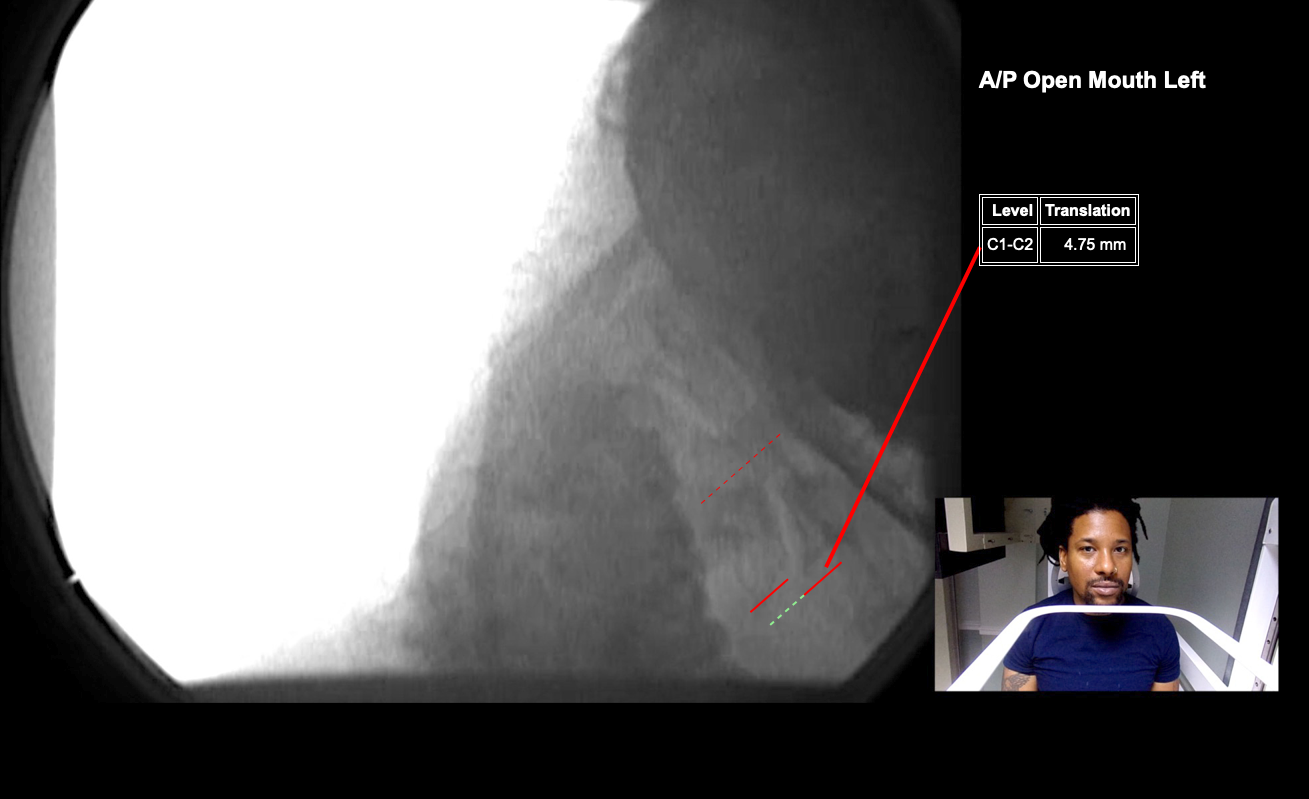

Image Name Image Type Image